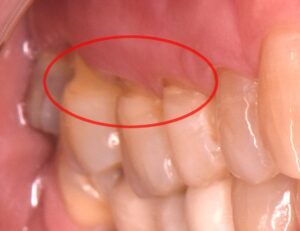

この場合、歯と歯茎の境目が欠け、神経が近くなったために知覚過敏が起こっていることがあります。

この状態は昔から「くさび状欠損」と呼ばれており、欠けた部分の形状が特徴的です。

NCCLは特に歯の頸部(歯茎に近い部分)の欠損に関連していると考えられています。

そのため、NCCL(くさび状欠損)の原因は酸蝕や摩耗など、さまざまな要因が組み合わさった多因子疾患だと考えられています。今後も、噛み合わせが関与するかどうかについては議論が続くでしょう。